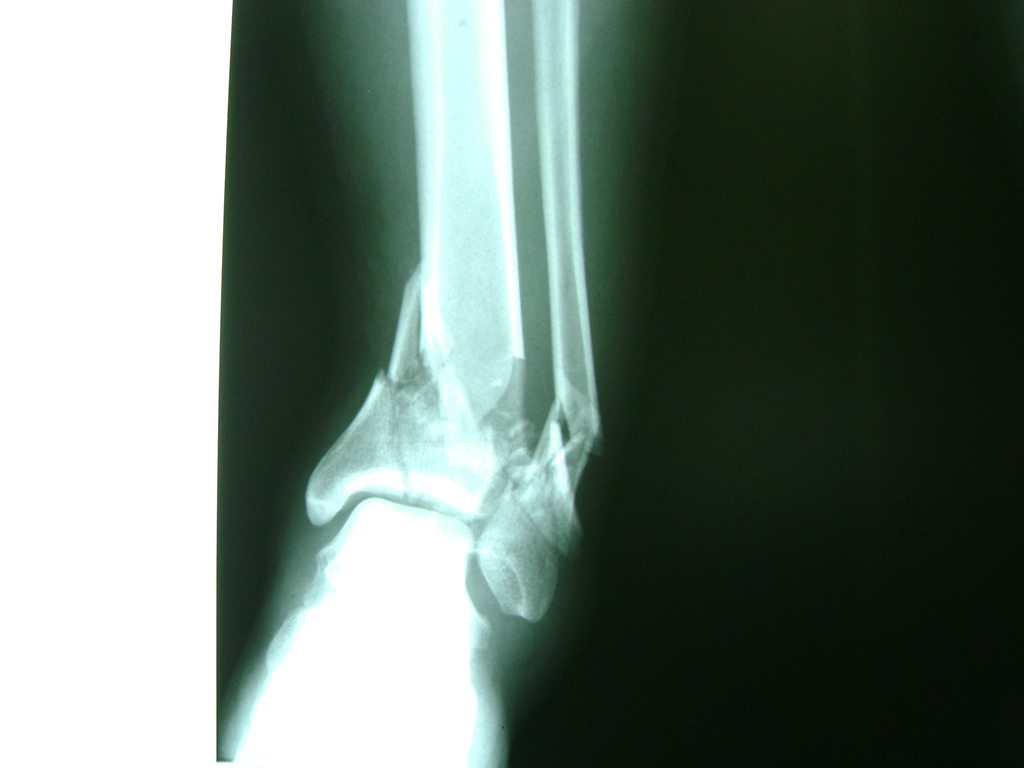

Una fractura de tobillo es la rotura de uno o más de los huesos del tobillo. Estas fracturas pueden ser:

Algunas fracturas de tobillo pueden requerir cirugía si:

• Los extremos de los huesos están desalineados entre sí (desplazados).

• La fractura se extiende hasta la articulación del tobillo (fractura intra-articular).

• Los tendones o ligamentos (tejidos que sujetan los músculos y los huesos entre sí) están rotos.